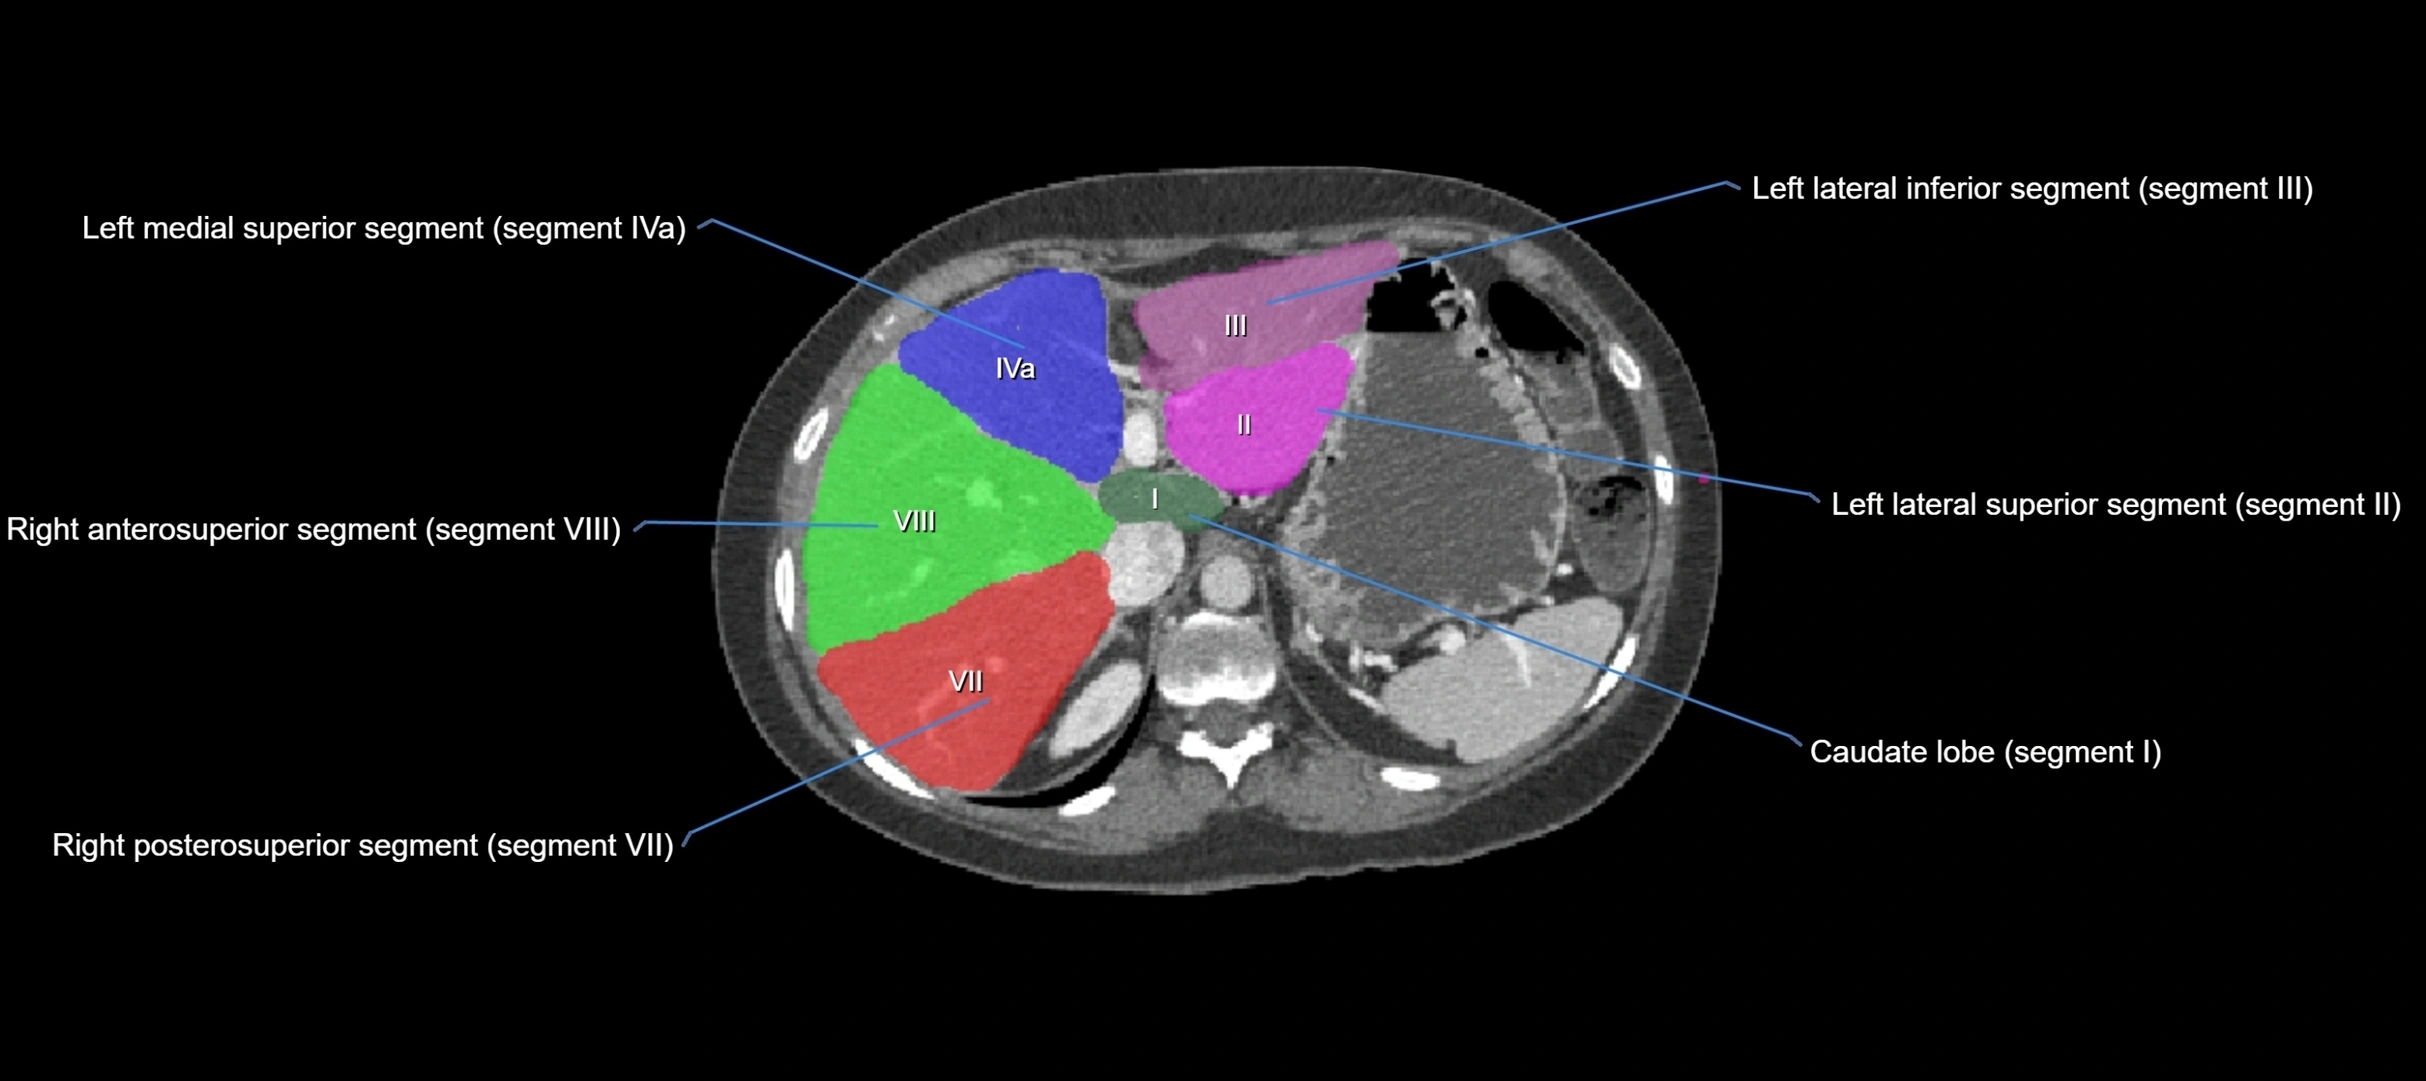

The caudate lobe of the liver is a distinct anatomical subdivision of the liver, designated as segment I in Couinaud’s classification. It lies on the posterior surface of the liver, between the fissure for the ligamentum venosum (left boundary) and the groove for the inferior vena cava (IVC) (right boundary). Superiorly, it is related to the posterior liver surface, and inferiorly it is separated from the left lobe by the porta hepatis.

The caudate lobe is unique because it receives dual portal venous and arterial inflow from both the right and left portal veins and hepatic arteries. It also has independent venous drainage directly into the IVC via multiple small hepatic veins, unlike other lobes that drain through the three main hepatic veins.

This anatomical autonomy makes the caudate lobe especially significant in liver surgery, transplantation, and hepatic venous outflow obstruction syndromes (e.g., Budd–Chiari syndrome). Enlargement of the caudate lobe is a characteristic imaging feature in chronic liver disease and cirrhosis.

• Segment I (Couinaud classification)

CT Image

image